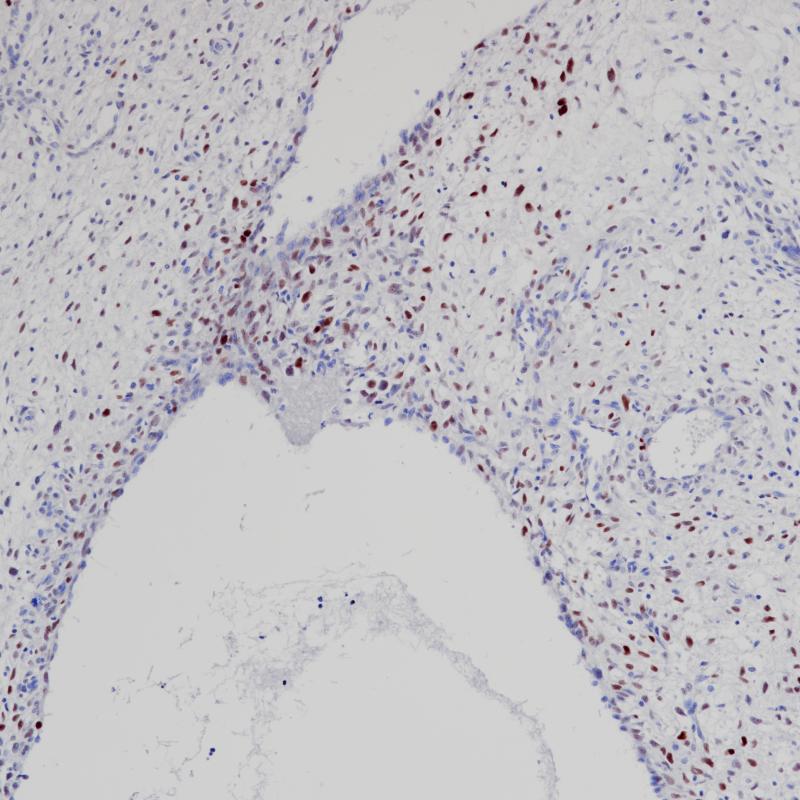

Topoisomerase II-α 重组兔单克隆抗体

阳性对照

宫颈癌

亚细胞定位

细胞核